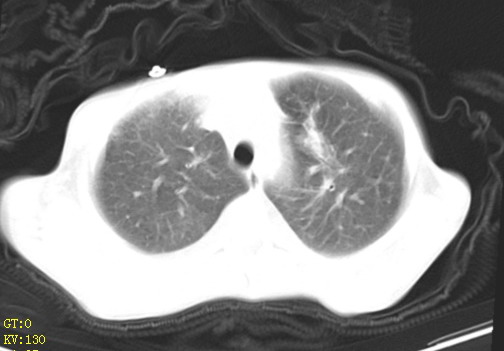

女,12岁,气促、咳嗽2天,3个月前查胸片示:两肺感染,急诊入院查ct,血常规等未检查。

左肺上叶改变考虑继发性肺结核,余双肺重症肺炎不排除h1n1。双侧胸腔少量积液。

双肺中下野不规则片絮状阴影,中外带明显,双侧胸腔少量积液,心影增大,心腔密度减低,隆突下及左侧气管旁见钙化淋巴结影,考虑双肺感染、心衰;建议结合临床除外h1n1并急性心衰,先心不能排除。

两肺多发片絮状模糊影,以下肺外带居多,内见支气管气像,纵膈窗未减影,两侧胸腔积液,心影增大,结合心超,支持重症肺炎,非常时期,甲型h1n1流感不排除。